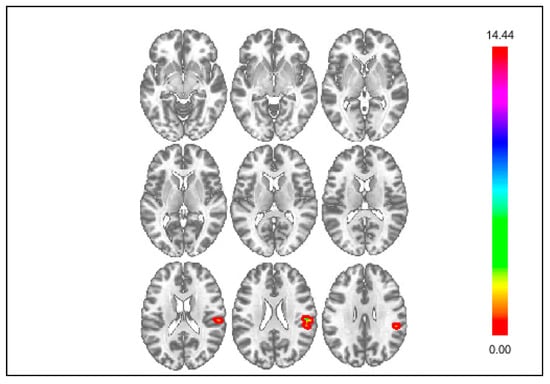

3.2. Results of Exploratory Connectivity Analyses

| Seed | Cluster Location | Cluster Size | Coordinates | Statistic | ||

| kE | x | y | z | Z | ||

| Social Rejection | ||||||

| DS Seed | Cerebellum | 77 | +06 | −84 | −42 | 4.34 |

| mPFC Seed | Central Opercular Cortex | 102 | −57 | −21 | +15 | 5.12 |

| Insula Seed | n.s. | --- | --- | --- | --- | --- |